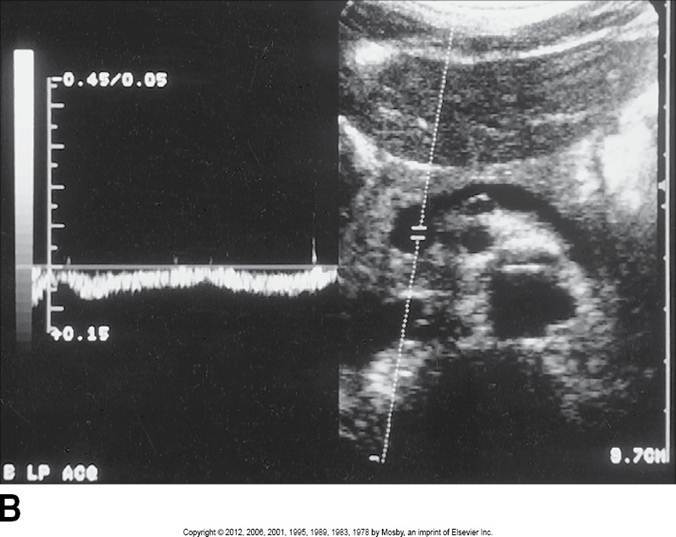

Proximal aorta

High systolic peak

Low diastolic comp.

Clean window